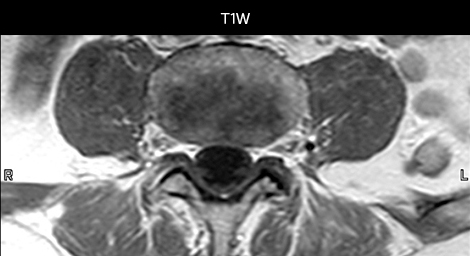

„Mit mDIXON TSE-Sequenzen ist es dank der T2-gewichteten Bilder auf Wasserbasis aus derselben Erfassung möglich, gleichzeitig morphologische Veränderungen aus den T2-gewichteten In-Phase-Bildern zu charakterisieren und ödematöse Veränderungen darzustellen. Auf diese Weise können anatomische und morphologische Befunde wie eine partielle oder komplette Bandruptur, ein knöcherner Ausriss oder ein Hämatom abgeklärt werden.“ „In Bezug auf die Beurteilung von Weichteilgewebe bietet mDIXON ähnliche Vorteile. Bei einer T2-gewichteten mDIXON TSE-Erfassung helfen die multiplen Kontraste zum Beispiel bei der Abklärung von pathologischen Befunden in Faserbündeln der peripheren Nerven, die auf anatomischen oder entzündlichen Veränderungen beruhen können.“ „Bei peripheren Gelenken erhalten wir mit mDIXON TSE eine gute Qualität in diffizilen Bereichen. Bilder mit Fettsuppression erscheinen vollständig homogen, auch bei einer großen Abdeckung mit 3,0 T – zum Beispiel beim Schulter- oder Beckengürtel – bzw. in den Gelenkflächen oder um Metallprothesen herum*, wo eine Fettsuppression mit STIR oder spektraler Suppression häufig unzureichend ist und zu Schwierigkeiten bei der Diagnose führt. Wenn ein diagnostisches Bild auf Anhieb richtig dargestellt wird, ist es nicht nötig, eine Sequenz zu wiederholen oder hinzuzufügen.“ „Mit mDIXON TSE-Sequenzen ist es dank der T2-gewichteten Bilder auf Wasserbasis aus derselben Erfassung möglich, gleichzeitig morphologische Veränderungen aus den T2-gewichteten In-Phase-Bildern zu charakterisieren und ödematöse Veränderungen darzustellen. Auf diese Weise können anatomische und morphologische Befunde wie eine partielle oder komplette Bandruptur, ein knöcherner Ausriss oder ein Hämatom abgeklärt werden.“ „In Bezug auf die Beurteilung von Weichteilgewebe bietet mDIXON ähnliche Vorteile. Bei einer T2-gewichteten mDIXON TSE-Erfassung helfen die multiplen Kontraste zum Beispiel bei der Abklärung von pathologischen Befunden in Faserbündeln der peripheren Nerven, die auf anatomischen oder entzündlichen Veränderungen beruhen können.“